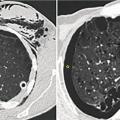

Épanchement pleural droit, ostéolyse vertébrale, abcès prévertébral

EPANCHEMENT PLEURAL

OSTEOLYSE

ABCES